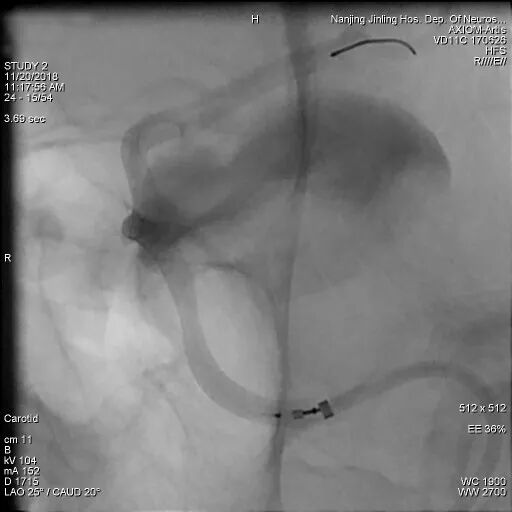

左侧颈内动脉海绵窦段巨大动脉瘤,余颅内血管未见明显异常。

为什么要用到微导管张鑫教授:“球囊锚定微导管辅助到位”技术在Pipeline Flex治疗复杂动脉瘤手术中的应用_https://www.jmylbn.com_新闻资讯_第1张

为什么要用到微导管张鑫教授:“球囊锚定微导管辅助到位”技术在Pipeline Flex治疗复杂动脉瘤手术中的应用_https://www.jmylbn.com_新闻资讯_第2张

为什么要用到微导管张鑫教授:“球囊锚定微导管辅助到位”技术在Pipeline Flex治疗复杂动脉瘤手术中的应用_https://www.jmylbn.com_新闻资讯_第3张